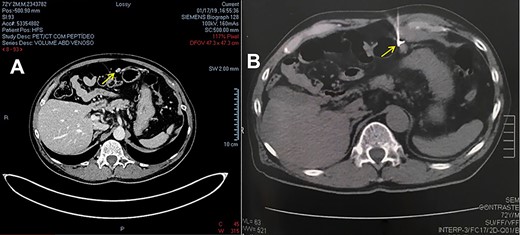

The disease remained stable until 2019, when the second consecutive increase in total PSA appeared, being 0.6 ng/mL on 11/26/2018 and 0.81 ng/mL on 01/07/2019. A Gallium-68 prostate-specific membrane antigen positron emission tomography (PET/CT-PSMA) imaging was performed, which showed a peritoneal nodule in the epigastric region, below the stomach and in front of the transverse colon, measuring 1.0 × 0.7 cm, with a significant increase in the expression of the specific antigen of prostate membrane – PSMA (SUV = 18.9). Due to the condition, suspicion of an implant was raised.

After a multidisciplinary team discussion with clinical oncology, surgical oncology and nuclear medicine followed by the patient’s free and informed consent, it was decided to perform diagnostic and therapeutic laparoscopy guided by the radioisotope. The lesion was marked with 0.5 mCi (18,5 MBq) of the radiopharmaceutical MAA-99mTc (macro aggregated human serum albumin) guided by computed tomography and confirmed by a SPECT image (single-photon emission computed tomography). This last image revealed a focal radiotracer concentration area in the upper left abdomen, measuring 3.5 and 5 cm deep from the skin, which did not change its appearance along with the scintigraphic evaluation (Fig. 1).

(A) CT image from PET-CT with PSMA-Gallium 68. (B) CT image of lesion marking with MAA-99mTc.